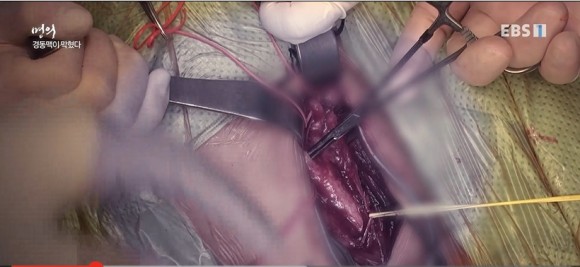

목 옆 피부를 절개하여 경동맥을 찾아 혈관을 막고 있는 플라크를 제거합니다.플라크란? 지방과 콜레스테롤이 뒤얽힌 조직

경동맥내막절제술 #경동맥내막절제술은 뇌로의 혈류가 끊기지 않도록 보조관을 연결하여 피를 통한 후 플라크가 있는 부분을 열어주면 내막을 절제합니다.

경동맥을 막고 있던 플라크